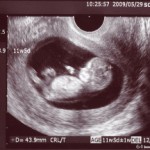

Tak wygląda płód w 11 tygodniu (klikalny):

USG w 11 tygodniu pokaże wyraźnie zarysy małego człowieka. Na wysokiej klasy sprzęcie ze szczególnie dobrą lokalizacją dziecka możesz już określić jego płeć. Jednak dane mogą być niedokładne.